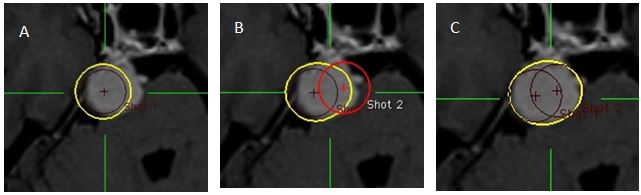

Chú thích: Các ví dụ về các hình elip và quả tạ. (A) Đường đồng liều 50% (vàng) của shot đơn 8 mm. (B) Một shot 8mm thứ hai được đặt gần để tạo ra một đường đồng liều có hình elip. (C) Một hình elip không đồng tâm dạng quả lê có thể được tạo ra nếu shot thứ hai lớn hơn (trong trường hợp này là shot 14 mm). (D) Một shot 8 mm thứ hai được đặt xa hơn shot thứ nhất để tạo ra đường đồng liều hình quả tạ. (E) Một shot thứ hai được đặt xa hơn shot thứ nhất nhằm mục đích tạo ra một “thanh” dài hơn của quả tạ nhưng sự tái chuẩn hóa lại tạo thành hai hình tròn. (F) Một shot nhỏ hơn có trọng số thấp hơn được sử dụng như một “shot tăng cường” để kết nối hai đường đồng liều (shot thứ ba là một shot 4 mm với trọng số 0.33).

Thủ thuật 10: Hình thành các đường ovan và đường hình chuông:

Hình 9: Hình ảnh tạo đường đồng liều hình quả tạ

Bệnh nhân Nguyễn Đ. V.; nam, 38 tuổi. Chẩn đoán: U màng não góc cầu tiểu não (P). Chỉ định xạ phẫu dao gamma quay (RGK) liều 18Gy